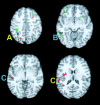

Functional magnetic resonance imaging (fMRI) was used to determine whether performance on lexical tasks was correlated with cerebral activation patterns. We found that such relationships did exist and that their anatomical distribution reflected the neurocognitive processing routes required by the task. Better performance on intramodal tasks (determining if visual words were spelled the same or if auditory words rhymed) was correlated with more activation in unimodal regions corresponding to the modality of sensory input, namely the fusiform gyrus (BA 37) for written words and the superior temporal gyrus (BA 22) for spoken words. Better performance in tasks requiring cross-modal conversions (determining if auditory words were spelled the same or if visual words rhymed), on the other hand, was correlated with more activation in posterior heteromodal regions, including the supramarginal gyrus (BA 40) and the angular gyrus (BA 39). Better performance in these cross-modal tasks was also correlated with greater activation in unimodal regions corresponding to the target modality of the conversion process (i.e., fusiform gyrus for auditory spelling and superior temporal gyrus for visual rhyming). In contrast, performance on the auditory spelling task was inversely correlated with activation in the superior temporal gyrus possibly reflecting a greater emphasis on the properties of the perceptual input rather than on the relevant transmodal conversions.